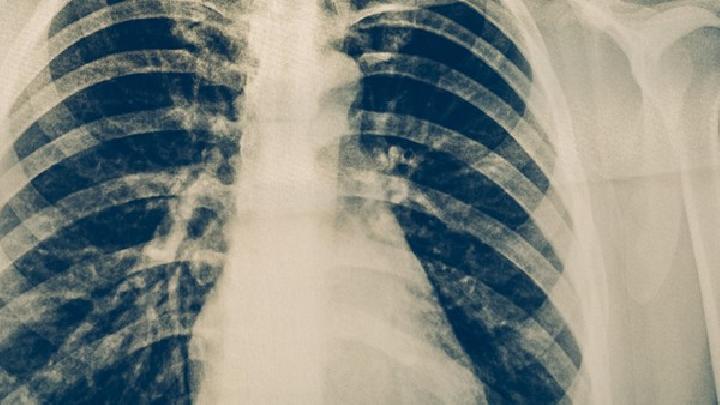

小儿肺气肿可急可缓,早期时可能无症状或是劳动后出现气短、呼吸困难、乏力、体重下降,后期可能出现心率加快、气短加剧,若出现这种情况,家长一定要重视,尽快选择正规医院检查、治疗,才能把疾病危害控制到最小,除了治疗外,平时保健也很重要,小儿肺气肿如何正确运动?